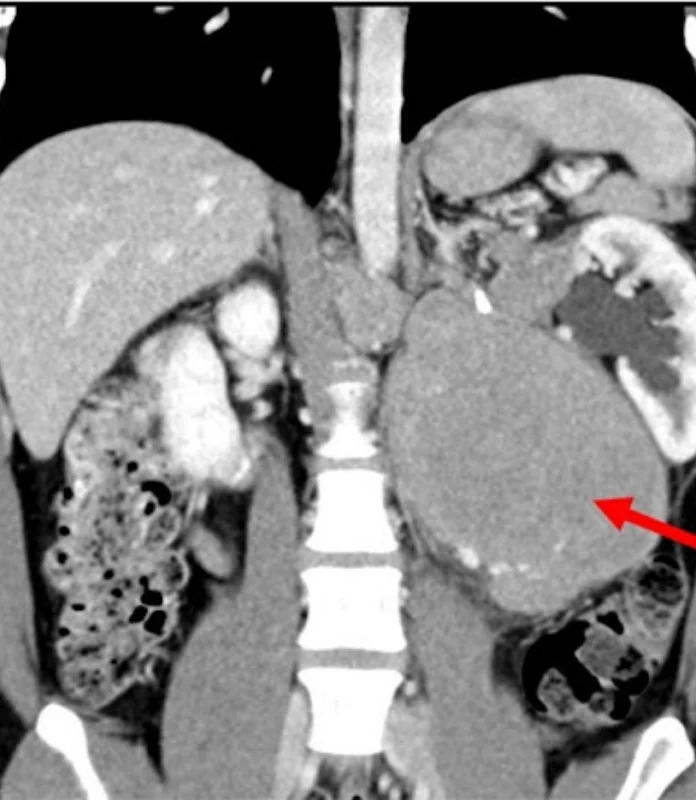

Retroperitoneal tumors develop in the space behind the abdominal organs, close to vital structures such as major blood vessels, kidneys, nerves, and intestines. Due to their location, these tumors often grow silently and are detected at an advanced stage. Under the care of Dr. Anuj Suketu, patients receive specialized evaluation and carefully planned surgery for retroperitoneal tumors. Each procedure is performed with precision, aiming for complete tumor removal while preserving nearby organs and maintaining quality of life.

Retroperitoneal tumour surgery involves the surgical removal of tumors arising in the retroperitoneal space, the area behind the abdominal lining.

Surgical planning is based on detailed imaging studies and multidisciplinary evaluation to ensure safe and effective treatment.

Experience with Challenging Tumor Locations

Skilled in managing tumors near vital organs and major blood vessels.